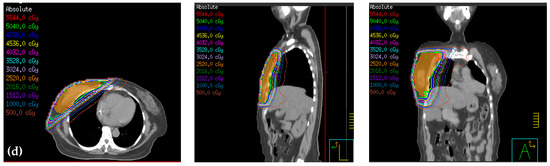

In the treatment of breast cancer, radiation pneumonitis (RP), in which the lung tissue in the irradiation field is damaged, may cause respiratory injury [41]. When the lung is irradiated V20Gy (%) of 20%, 21–25%, 26–30%, and >31%, the risk of developing RP in half year is 8.7%, <18.3%, 51%, and 85%, respectively [40]. When the lung is irradiated V20Gy (%) <22%, 22–30%, 31–40%, and >40%, the risk of developing RP in 2 years is 0%, <7%, 13%, and 36%, respectively [42]. In continuous partial arc, the mean ipsilateral lung dose is 10.10 Gy ± 2.5, V5Gy (%) is 50.3% ± 13.3, V10Gy (%) is 29.9% ± 8.0, and V20Gy (%) is 16.4%±4.8 [43]. In non-continuous partial arc, the mean ipsilateral lung dose is 8.22 Gy ± 0.57, V5Gy (%) is 40.46% ± 3.81, V10Gy (%) is 23.32% ± 2.07, and V20Gy (%) is 12.71% ± 2.23 [25]. Studies showed that, when the mean lung dose is <10 Gy, 10–20 Gy, 20–30 Gy, and >30 Gy, the risk of developing RP is 10%, 16%, 27%, and 44%, respectively [42,44]. In this study, the ipsilateral lung dose of treatment planning of continuous partial arc is the lowest among the four treatment plans, while IMRT is the largest. V20% in continuous partial arc is also the lowest. Our results are consistent with that of the above-mentioned studies and reports lower ipsilateral lung dose when continuous partial arc was applied. The main reason of the low dose lies in the higher conformity provided from dual arc for continuous partial arc. This technique can enhance dose modulation in the irradiation field and beam usage rate. Staring from the tangential angle, the beam irradiated along the chest wall, the dose weight limit for the lung can be achieved when designing the plan, and dose irradiation on the lung is reduced. On the other hands, the angle design for IMRT can be considered with target area shape. The close area can also be irradiated if the target area is extremely close to the lung. Although there is intensity modulation in the irradiation field, it forms mainly with MLC. Leaves in the MLC induce dose scattering and radiation leakage and may increase neighboring organ dose (Figure 5).

Figure 5.

Dose distribution of (a) IMRT, (b) hybrid 3D-CRT/IMRT, (c) non-continuous partial arc, and (d) continuous partial arc.